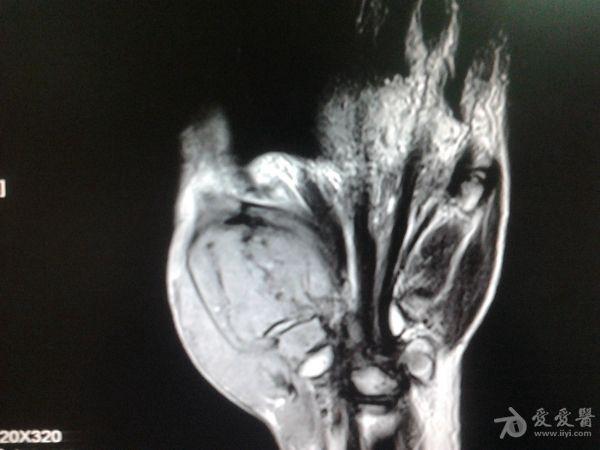

右第一掌骨、大多角骨肿瘤

男性患者,81岁,右手肿痛3个多月。无任何其它症状。体查:右手第一掌骨部肿胀明显,第一指活动受限,余四指活动可,腕关节活动小部分受限,活动时会痛。影像学检查如下。活检示:弥漫性大B细胞淋巴瘤。大家看看需不需要截肢?现在有人主张手术;有人主张不手术,直接化疗。大家有什么看法?

从以上资料看已经影响到腕关节了,还是截吧,不能姑息